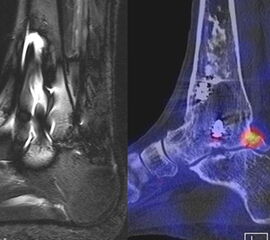

In Abbildung 3.4. ist ein typisches Beispiel für ein symptomatisches Os trigonum dargestellt.

Zum Lesen der Bildbeschreibung und zur Vollansicht bitte das Bild anklicken. Bild: H. C. Rischke

Bei der Differenzialdiagnose von Impingement-Syndromen am Sprunggelenk kann das SPECT/CT den Ort der Symptome- verursachenden Stressreaktion darstellen 32. Eine typische Ursache für ein posteriores Impingement kann ein Os trigonum sein. Scherkräfte im Bereich der Synchondrose eines Os trigonum lösen hypermetabole Stressreaktionen aus. Die Exzision des Os trigonum stellt eine erfolgreiche Therapie dar, sodass der Befund eines szintigraphisch aktivierten Os trigonum den Erfolg einer chirurgischen Therapie vorhersagen kann 3334.